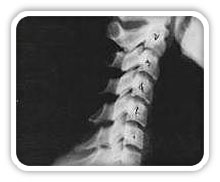

Phase Two Subluxation Degeneration

Phase two subluxation degeneration is normally seen in subluxations that have been present between 20 and 40 years. This phase has some of the same characteristics of the previous phase including a loss of normal curvature and position as well as an alteration in segmental motion. In addition, spines with Phase Two Subluxation Degeneration many times show a reduction in the patient's range of motion in that area. X-rays of a phase two begin to show calcium changes or buildup at certain levels of the spine. These changes are sometimes called by many names including spurs and arthritis. Disc spaces between the affected vertebrae are noticeably narrower and may appear to be flattening out. Although most people with Phase Two Subluxation Degeneration may not exhibit any symptoms, some may start to feel stiff or achy. Chiropractic reconstructive care for patients in phase two ranges from 1.5 years to 2.5 years. Again, if Phase Two Subluxation Degeneration is left uncorrected it slowly advances to the next phase.